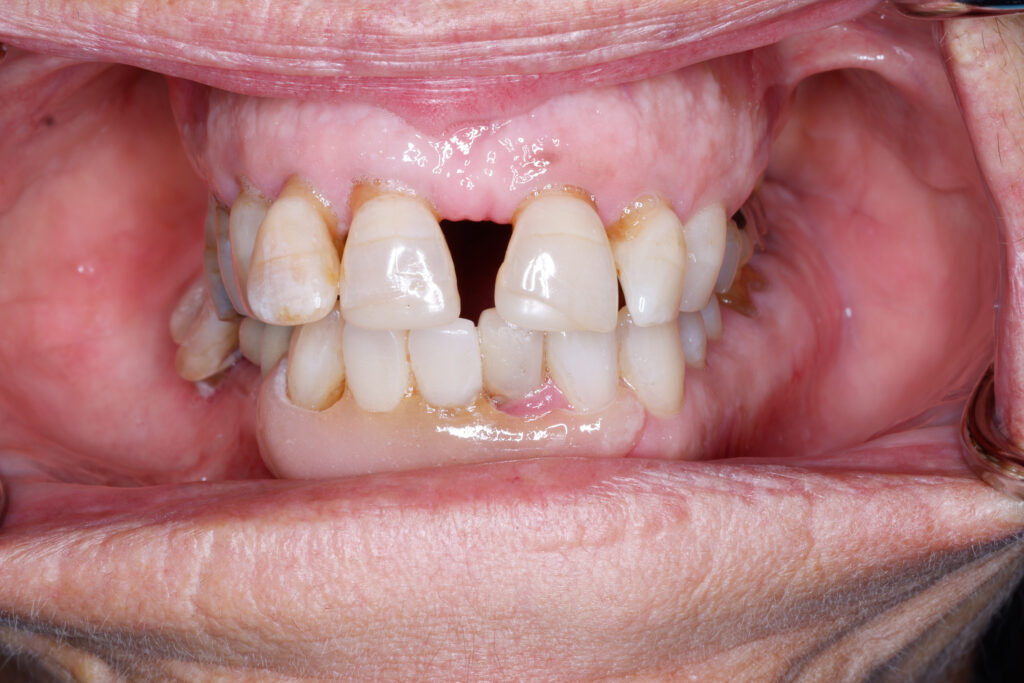

Before

After